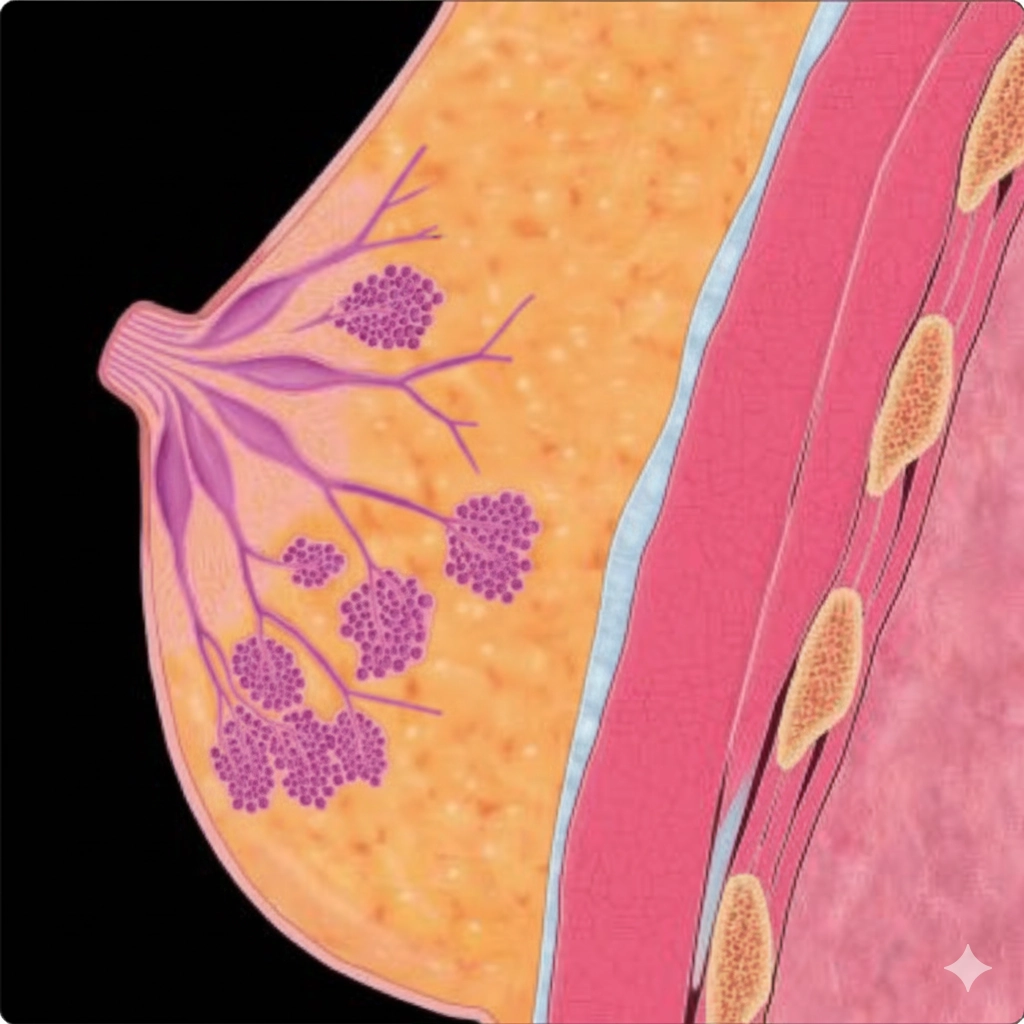

• Tuyến vú